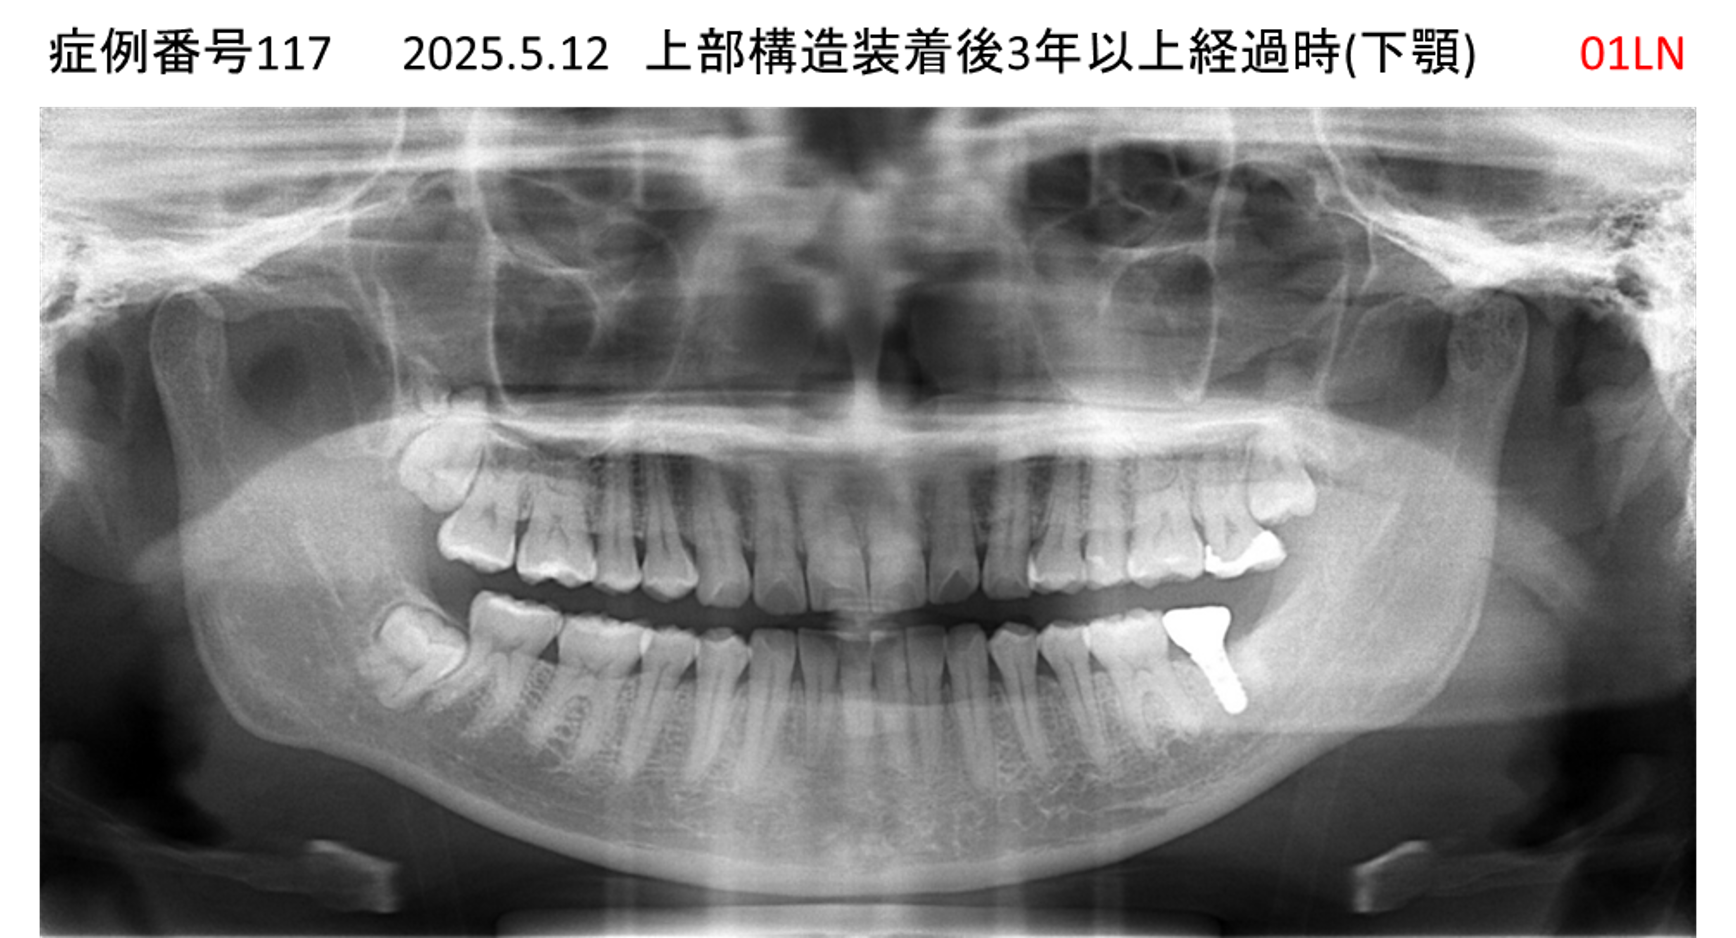

奥歯で噛めない患者様のインプラント症例

| 治療名称 |

インプラント |

| 治療費用 |

150万円+税 |

| 治療期間 |

3か月 |

| 患者さんの症状(主訴) |

奥歯で噛めない。食事がとれない。 |

| 治療内容 |

| 治療結果 |

食事に困らない。何でも食べられる。 |

| 治療の注意点(リスク/副作用) |

インプラントが壊れたら再治療が必要 |